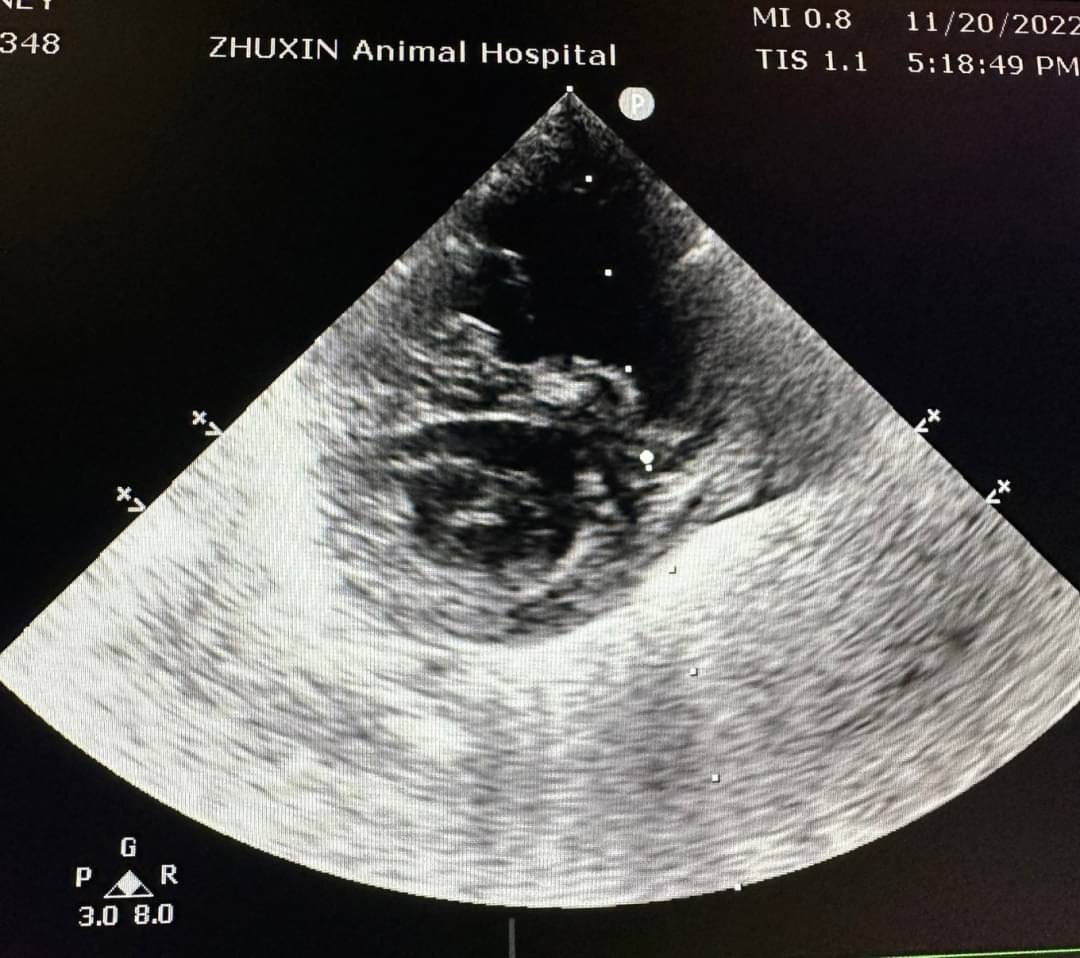

腹腔超音波下出現腹水,肝臟腫大伴隨肝門靜脈擴張。腹水檢測為漏出液,抹片下為少量發炎細胞,並無看到細菌。針對X光下心臟變大的影像,安排後續心臟超音波檢查,診斷為肺部高壓誘發肝門靜脈壓力上升引發腹水出現。心電圖下並無明顯心律不整。